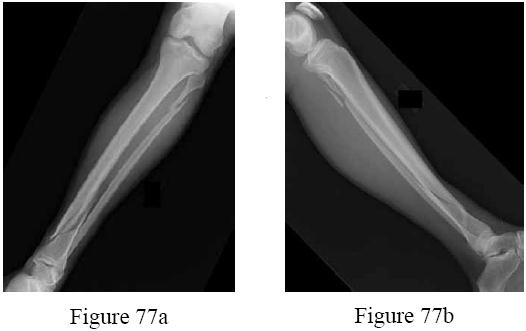

-are the radiographs of a 45-year-old man who fell into a ditch and sustained a twisting injury to the left lower extremity. Examination in the emergency department reveals normal neurologic function, no skin compromise, and palpable pedal pulses. The patient has no other complaints and has an otherwise normal examination. What additional imaging study is recommended?